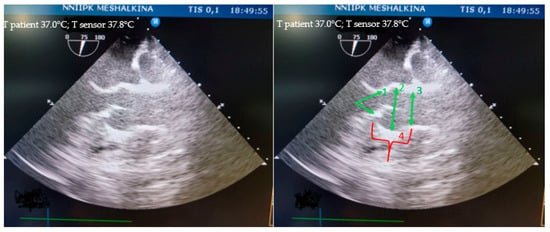

All of the animals’ structures, such as the fibrous ring of the aortic valve, the sinus of Valsalva, and the sinotubular junction, were clearly identified by transesophageal echocardiography (Figure 4).

Figure 4. Visualization of the aortic root in mini pigs on TEE: 1—fibrous ring of the aortic valve; 2—sinus of Valsalva; 3—sinotubular junction; 4—height of the aortic root.